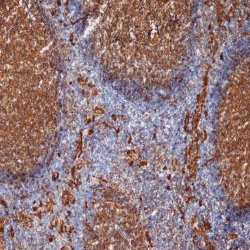

WB (Western Blot), FCM/FACS (Flow Cytometry), IHC (Immunohistochemistry)

(Staining of human peripheral blood monocytes with Mouse anti Human CD9: Alexa Fluor 647)

Mouse anti Human CD9 antibody, clone MM2/57 recognizes human Leukocyte antigen MIC3 also known as MRP-1 or CD9. CD9 is a 228 amino acid multi pass membrane glycoprotein belonging to the tetraspanin family with a molecular weight of ~24kDa expressed by platelets, monocytes, some lymphocytes and endothelial cells. Mouse anti Human CD9 antibody, clone MM2/57 recognizes a conserved epitope on CD9 present on a wide range of mammalian species.